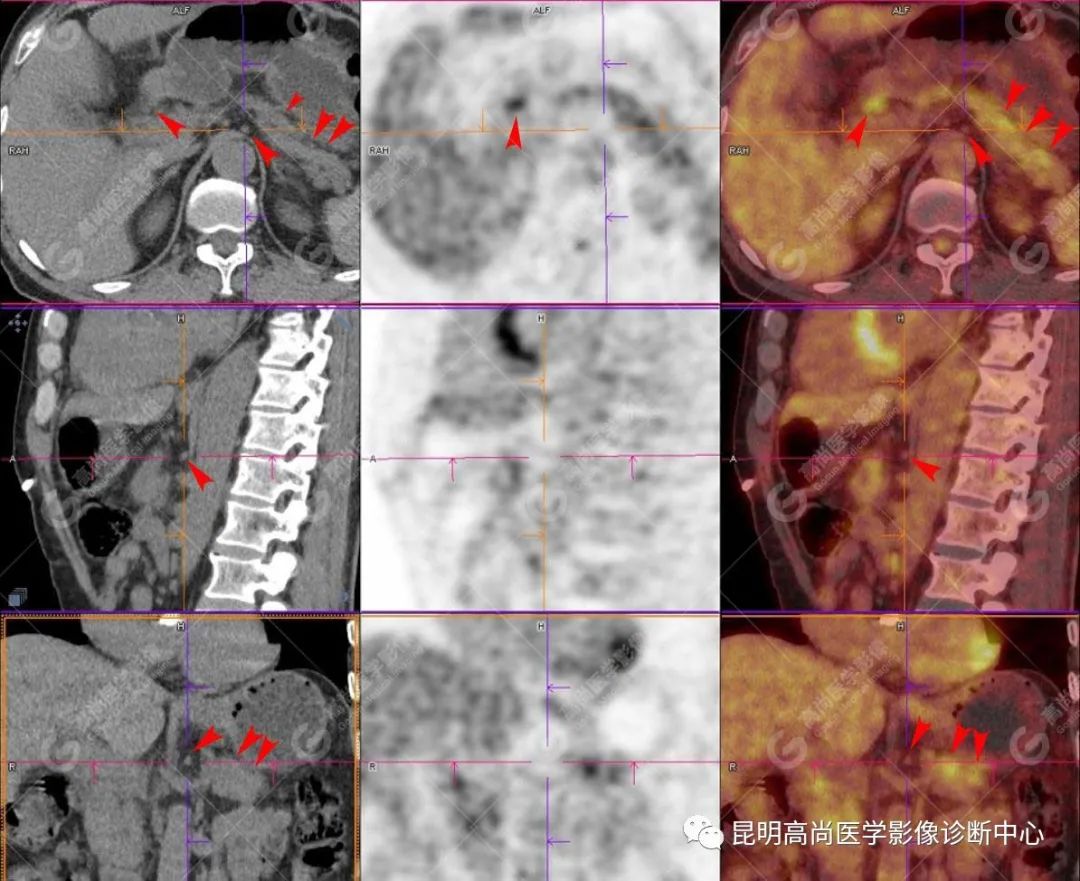

检查图像

影像诊断

十二指肠壶腹区等密度结节影伴糖代谢持续增高,多考虑恶性病变(壶腹癌),继发主胰管扩张及慢性胰腺炎表现;腹膜后多发淋巴结显示,糖代谢不同程度增高,不除外转移。

(4)18F-FDG PET/CT

在诊断胰腺癌方面具有较高的敏感性,其敏感性可达 85%~90%,特异性可达 55.6%~94%;尤其在鉴别良恶性的囊性肿瘤时,其准确率可达到 94%~95%;PET/CT 是胰腺癌的主要检查手段,它比常规 CT 和 MRI 更具优势,可早期发现远处转移灶;同时可以作为一个独立的、用于预测胰腺癌生存和无进展生存的独立的指标,即 SUV,代谢肿瘤体积,即 MTV。